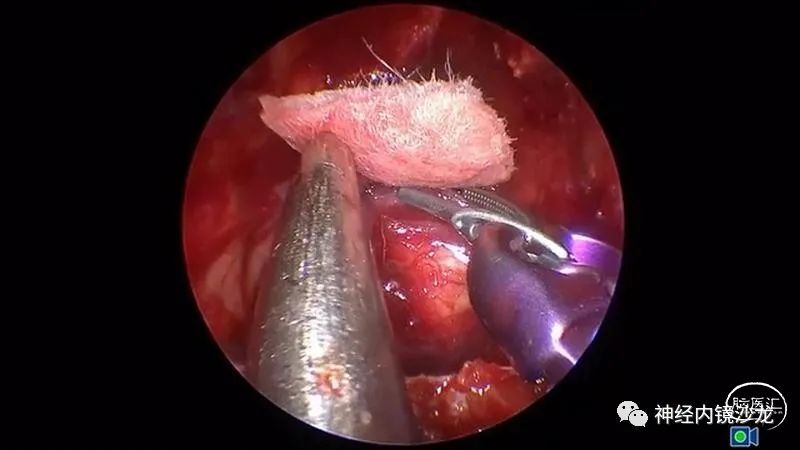

手术暴露充分术野,从蝶骨平台到斜坡,从眼眶到眼眶。切除大块钙化部分肿瘤后,我们找到肿瘤包膜和下丘脑、视觉通路之间的清晰的分离平面。切除结束时,发生了后交通动脉从大脑后动脉撕脱导致的动脉出血。采用单轴持夹器放置一个成角的动脉瘤夹,以夹闭损伤部位并保证供血动脉不狭窄。术后即刻和晚期磁共振成像和CTA检查显示肿瘤全切、无卒中、无假性动脉瘤形成。